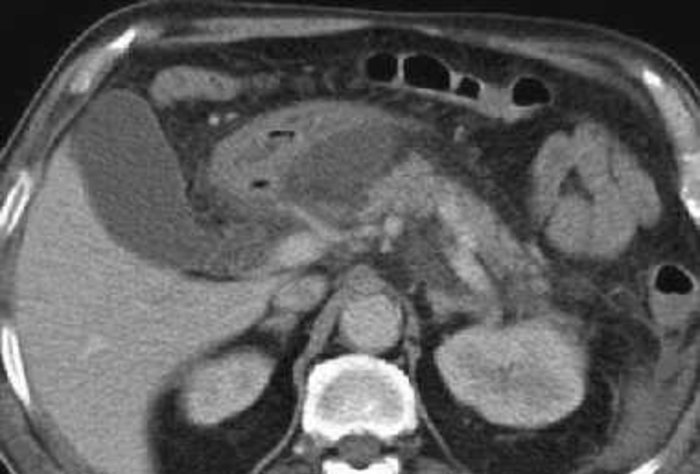

Curso de Imagenología - "Tomografía Computada de Abdomen Agudo"

Actualización de la Guía de Manejo de Antimicrobianos en la Asociación Española: Infecciones Abdominales.

El jueves 1º de diciembre se realizó una charla de actualización en Infecciones Abdominales